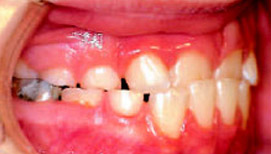

Elasto-Aligner

Aligner означает «выравниватель». Он, как и все эластопозиционеры, может применяться для лечения взрослых, так как зубы в течение жизни подвержены смещению. Разнообразие возможностей его применения – от самостоятельного лечебного аппарата до ретейнера на заключительном этапе лечения с целью точной постановки окклюзионных контактов – делает Aligner наиболее популярной моделью из всех эластопозиционеров (рис. 1).

Эласто-Aligner делает возможным широкий диапазон перемещения зубов за короткое время

Это обусловлено в первую очередь А-силиконовым базисным материалом Silasto 70: по своей высокой способности возврата в исходное положение он превосходит все похожие материалы, так как позволяет обеспечить широкий диапазон перемещения зубов в относительно короткое время. Аппарат следует носить днем как минимум два часа, а также в течение ночи (рис.1). Эласто-Aligner используется независимо от возраста. Если необходима коррекция положения нижней челюсти, то, как и все двухчелюстные аппараты, он стимулирует ее горизонтальный рост. Установка нижней челюсти в нейтральное положение или коррекция центральных линий путем латерального смещения нижней челюсти осуществляется с помощью артикулятора, после того как было определено положение верхней челюсти относительно черепа и зарегистрировано положение нижней челюсти.